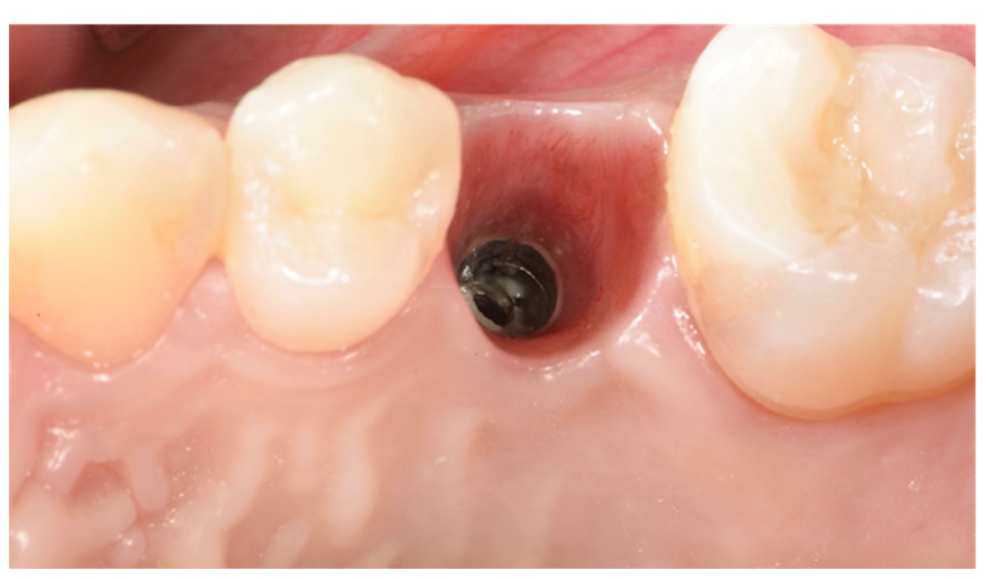

Implants fracture is an untreatable condition. There are several tools that may help clinician to remove the implant. However, fractured implant often presented damaged implant-abutment connection, hence, implant retrieval tools/kits (Figures 1–4) may not work. In cases implant is severely damaged and/or the residual osseointegration is very strong, such us in the mandible, the only possibility is to use a trephine burs (Figures 5–10).